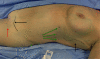

Lymphedema remains a poorly understood entity that can occur after lymphadenectomy. Herein, we will review the pathogenesis of lymphedema, diagnostic modalities and the natural history of extremity involvement. We will review the incidence of upper extremity lymphedema in patients treated for breast malignancies and lower extremity lymphedema in those treated for gynecologic malignancy. Finally, we will review traditional treatment modalities for lymphedema, as well as introduce new surgical treatment modalities that are under active investigation.